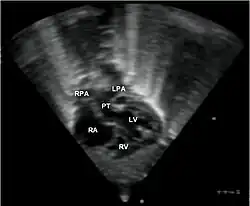

Badanie echokardiograficzne prawie zawsze potwierdza wstępne rozpoznanie i jest wystarczającym badaniem diagnostycznym. Cewnikowanie serca jest wykonywane tylko w przypadku potrzeby wyjaśnienia innych towarzyszących anomalii.